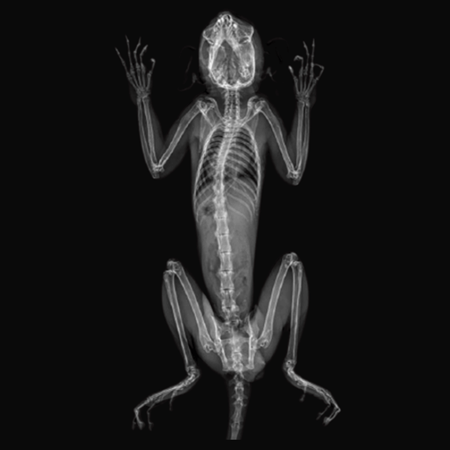

X-Ray Attenuation Image - Rat. Image Credit: Scintica Instrumentation Inc

With this noninvasive, nondestructive method, no contrast, substrate injection, or animal pretreatment is necessary. The 2D X-ray image can also be used with the iNSiGHT system to determine precise bone length measurements.